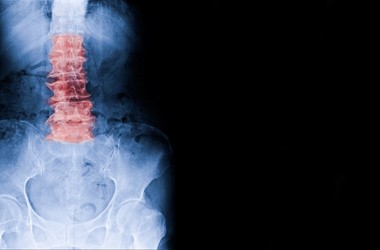

Lumbago, inaczej postrzał lub heksenszus, to zespół bólowy dotyczący odcinka lędźwiowo-krzyżowego kręgosłupa. Ból w dole pleców pojawiający się w przebiegu schorzenia jest spowodowany przeciążeniem struktur kręgosłupa, do którego może dojść np. na skutek dźwigania ciężkich przedmiotów, braku aktywności fizycznej, długotrwałego przyjmowania pozycji siedzącej lub stojącej, nadwagi i otyłości. Czynnikiem zwiększającym ryzyko wystąpienia postrzału są także zmiany zwyrodnieniowe kręgosłupa. Jakie są domowe sposoby walki z lumbago?

Lumbago (od łac. lumbalis – lędźwiowy) jest terminem ogólnym, który odnosi się do bólu w krzyżu i oznacza dolegliwości związane z nadmiernym przeciążeniem struktur kręgosłupa. Ze względu na stopień nasilenia bólu oraz jego nieprzewidywalność, taki stan określa się również mianem postrzału.

- ból kręgosłupa lędźwiowo-krzyżowego (ból pleców na dole),